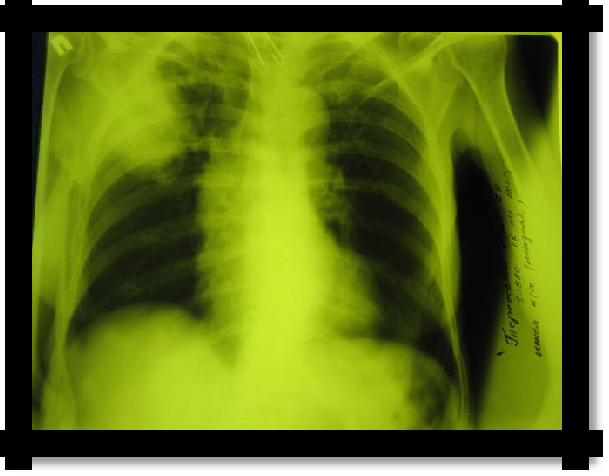

1. X-ray: a bright pulmonary field without pulmonary pattern, and closer to the root - the shadow of a compressed lung. With intense pneumothorax - displacement of the mediastinal organs to the healthy side;

1. With the simultaneous accumulation of liquid and air (Hydropneumothorax) in the pleural cavity, the horizontal upper limit of dullness corresponds to the level of the liquid. Dullness easily changes its boundary when changing the position of the patient's body. This border usually remains horizontal, with a loud tympanic sound above it. When succussion is determined by the noise of the splash (taking Hippocrates) in the chest.

Pic 2.6 Pneumothorax Pic 2.7 Hydropneumothorax